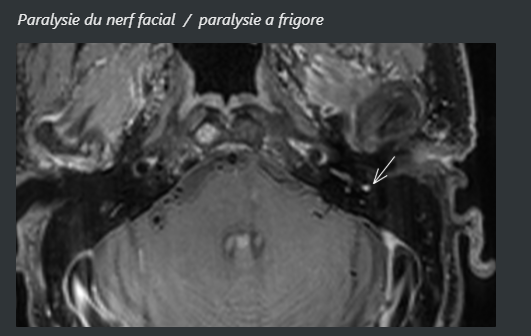

• Prise de contraste du nerf facial (proche du ganglion géniculé++)

4fe94bf3ed6f0a463dd3c34ab240b95a.png